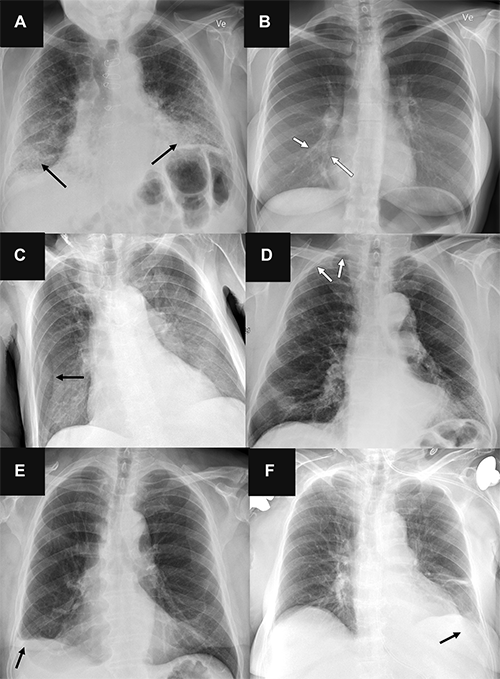

Beyond breath analysis, AI also enhances traditional diagnostic tools. In imaging, for example, AI algorithms scan CT, MRI, or X-ray images to detect tumours that may be too small or subtle for human eyes to reliably identify. By combining pattern recognition, predictive modelling, and large scale data analysis, AI assists clinicians in making accurate decisions.

AI in medical imaging and pathology

Radiologists are increasingly using artificial intelligence to improve the detection of diseases such as lung and prostate cancer. Algorithms identify small tumours or anomalies that might be missed by human experts, helping doctors increase their diagnostic accuracy.

How artificial intelligence influences radiology. Image via the Radiological Society of North America.

In recent years the integration of artificial intelligence into cancer diagnostic imaging has improved.

As a result, radiologists and oncologists are using artificial intelligence “co pilots” to help identify subtle tumours, quantify changes over time, and standardise interpretation, thus allow faster, more accurate diagnoses and potentially improving patient outcomes.